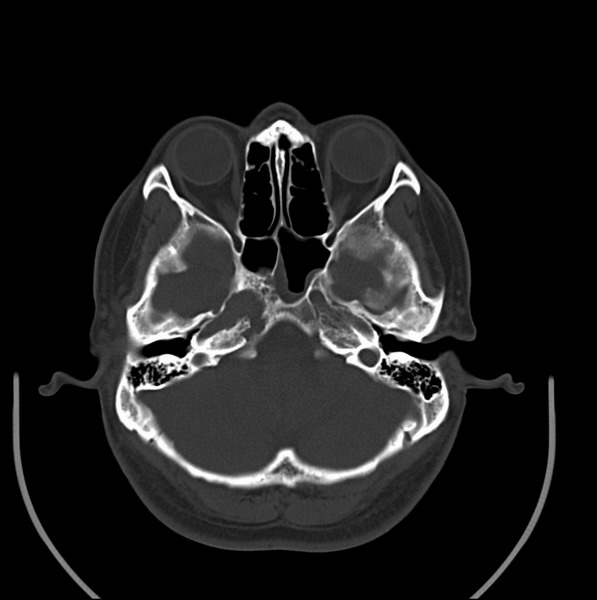

扫描示鼻咽腔不对称,中度狭窄,右侧咽隐窝消失,局部软组织肿块,鼻咽右侧壁增厚形成肿块,突入鼻咽腔,肿块平扫呈等密度,肿块向深部侵润,右侧翼内外肌受侵,右侧咽旁间隙变窄;向后生长,头长肌界线欠清,向后上生长侵犯同侧颈动脉鞘区。双侧海绵窦增宽,内见软组织影与鼻咽部肿块相连。考虑鼻咽癌。鼻咽癌主要是放射治疗,且效果较好;到当地有治疗设备较大医院治疗即可。

鼻咽部新生物(纤维血管瘤?鼻咽癌?)侵犯右侧中颅窝底及右侧海绵窦;建议必要时活检定性。

典型鼻咽癌侵犯右侧海绵窦(对放疗敏感)

还是先确诊,如果是鼻咽癌,一般行放射治疗;这例患者我首先考虑鼻咽癌